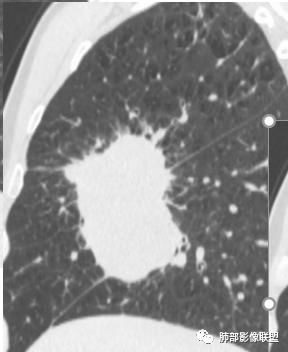

这一片病灶是右肺上叶,里面可以看的支气管走进去,然后纵隔淋巴结肿大,增强后有中度强化

首先临床资料没有特别提示。影像上首先背景是肺气肿背景,这个是肺癌的危险因素。

淋巴结肿大,且坏死,不均强化

病灶内不均匀强化。支气管堵塞

边缘膨隆。内血管毛糙纤细

中叶支气管堵塞,但是也有推移

跨叶,累及三个叶

下叶比较小,应该上往下突的,而且是直角突下来。不是像沿着是慢慢的,这个是直接下来

两种情况,第一是叶间裂这个地方正好缺如发育不好,第二是恶性肿瘤直接侵犯,这个显然是后者

周围小毛刺

小叶间隔增厚?